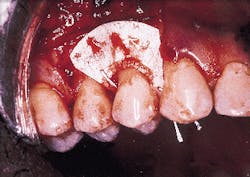

A patient with a periodontal abscess on the buccal of tooth #5 can be seen in photograph #1. Probing reveals a 6 mm pocket.

Photograph #1: An abscess is present on the facial aspect of tooth #5. Probing indicated a 6mm pocket.

Photograph #2: Subsequent to flap elevation a large piece of calculus is observed on the facial aspect of tooth #5.